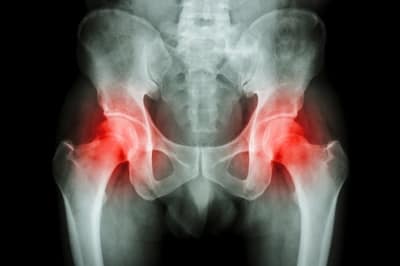

A healthy joint has a layer of articular cartilage covering the underlying bone, in OA there is a thinning of or damage to the articular cartilage which progressively worsens over time. As a reaction to the breakdown of the articular cartilage, bone spurs or osteophytes form. The result is that there is a progressive onset of joint stiffness, a loss of joint range of movement, pain and loss of function or disability.

Firstly there are multiple studies showing that findings on X rays, MRI and CT scans do not correlate strongly with the degree of symptoms that patients complain of. Therefore if you have been told that a scan or X ray shows “degenerative change” don’t assume that there is nothing that can be done.